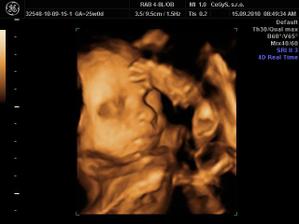

Náš anjelik🙂